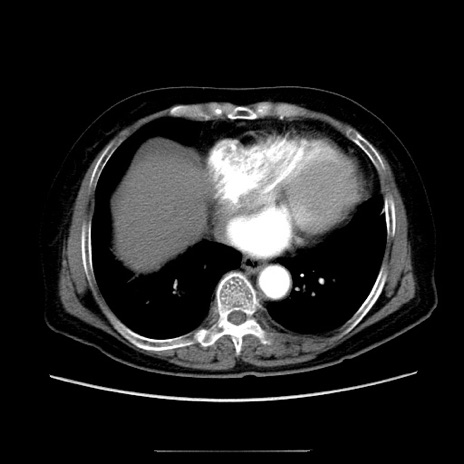

症例5(横断像)

【症例】70歳代女性

【主訴】お腹が張る

【現病歴】1週間くらい前から腹部膨満の自覚あり。昨日夜から増悪したため、本日救急外来受診。

【身体所見】意識清明、BT 36.5℃、BP 165/106mmHg、HR 80bpm、SpO2 98%、腹部:膨満、軟、自発痛・圧痛なし、触診にて不快感あり、腸蠕動音:減弱

【データ】WBC 12600、CRP 1.04